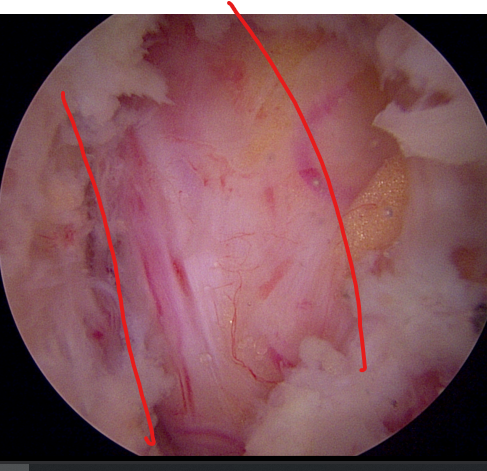

양방향 척추 내시경을 통한 다발성 척추 협착증의 치료 [온종합병원 척추센터 우영하 소장 ]

- 계획: 양방향 척추 내시경은 미세한 카메라와 도구를 사용하여 척수와 주변 신경 구조를 정밀하게 시각화할 수 있습니다. 이를 통해 정확한 진단을 내릴 수 있으며, 각 환자에게 맞는 개별적인 수술 계획을 수립할 수 있습니다.

- 소형 절개와 미세한 수술: 양방향 척추 내시경은 작은 절개를 통해 수술을 수행할 수 있습니다. 이는 환자의 회복 기간을 단축시키고 합병증의 위험을 줄입니다. 또한, 미세한 도구를 사용하여 정교한 조작이 가능하므로 척추 근육과 조직을 최소한으로 손상시키면서 치료할 수 있습니다.